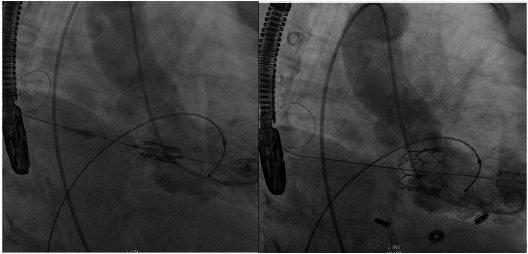

Se realizó bajo anestesia general y con apoyo de ecocardiografía transesofágica (ETE) con la cual se descartó la presencia de trombos. Con una minitoracotomía al nivel del quinto/sexto espacio intercostal anterior izquierdo y posterior apertura del pericardio, se aseguró con dos puntos de sutura concéntricas triangulares con prolene 3-0. Se realizó una punción directa del ápex y se avanzó una guía blanda que se intercambió por una guía ExtraStiff de 0,035” en la aurícula izquierda. Se corroboró bajo visión por ETE principalmente, ya que la válvula biológica implantada no nos proporcionaba bordes radiolúcidos como guía, de gran importancia para el posicionamiento; 6 esto se realizó en forma indirecta a través de un catéter cola de cerdo (pig tail) en el ventrículo izquierdo, la posición adecuada de la válvula Edwards balón-expandible SAPIENT XT número 26 (Figura 1), y, a través de marcapaseo rápido a 180 latidos por minuto, se expandió el balón y se desplegó la válvula, se controló por radioscopia, ventriculografía y ETE, su correcto funcionamiento, sin fugas paravalvulares, por lo que se dio por terminado el procedimiento en forma exitosa (Figura 2). La paciente pasó a unidad coronaria y a los 4 días fue dada de alta sin complicaciones.